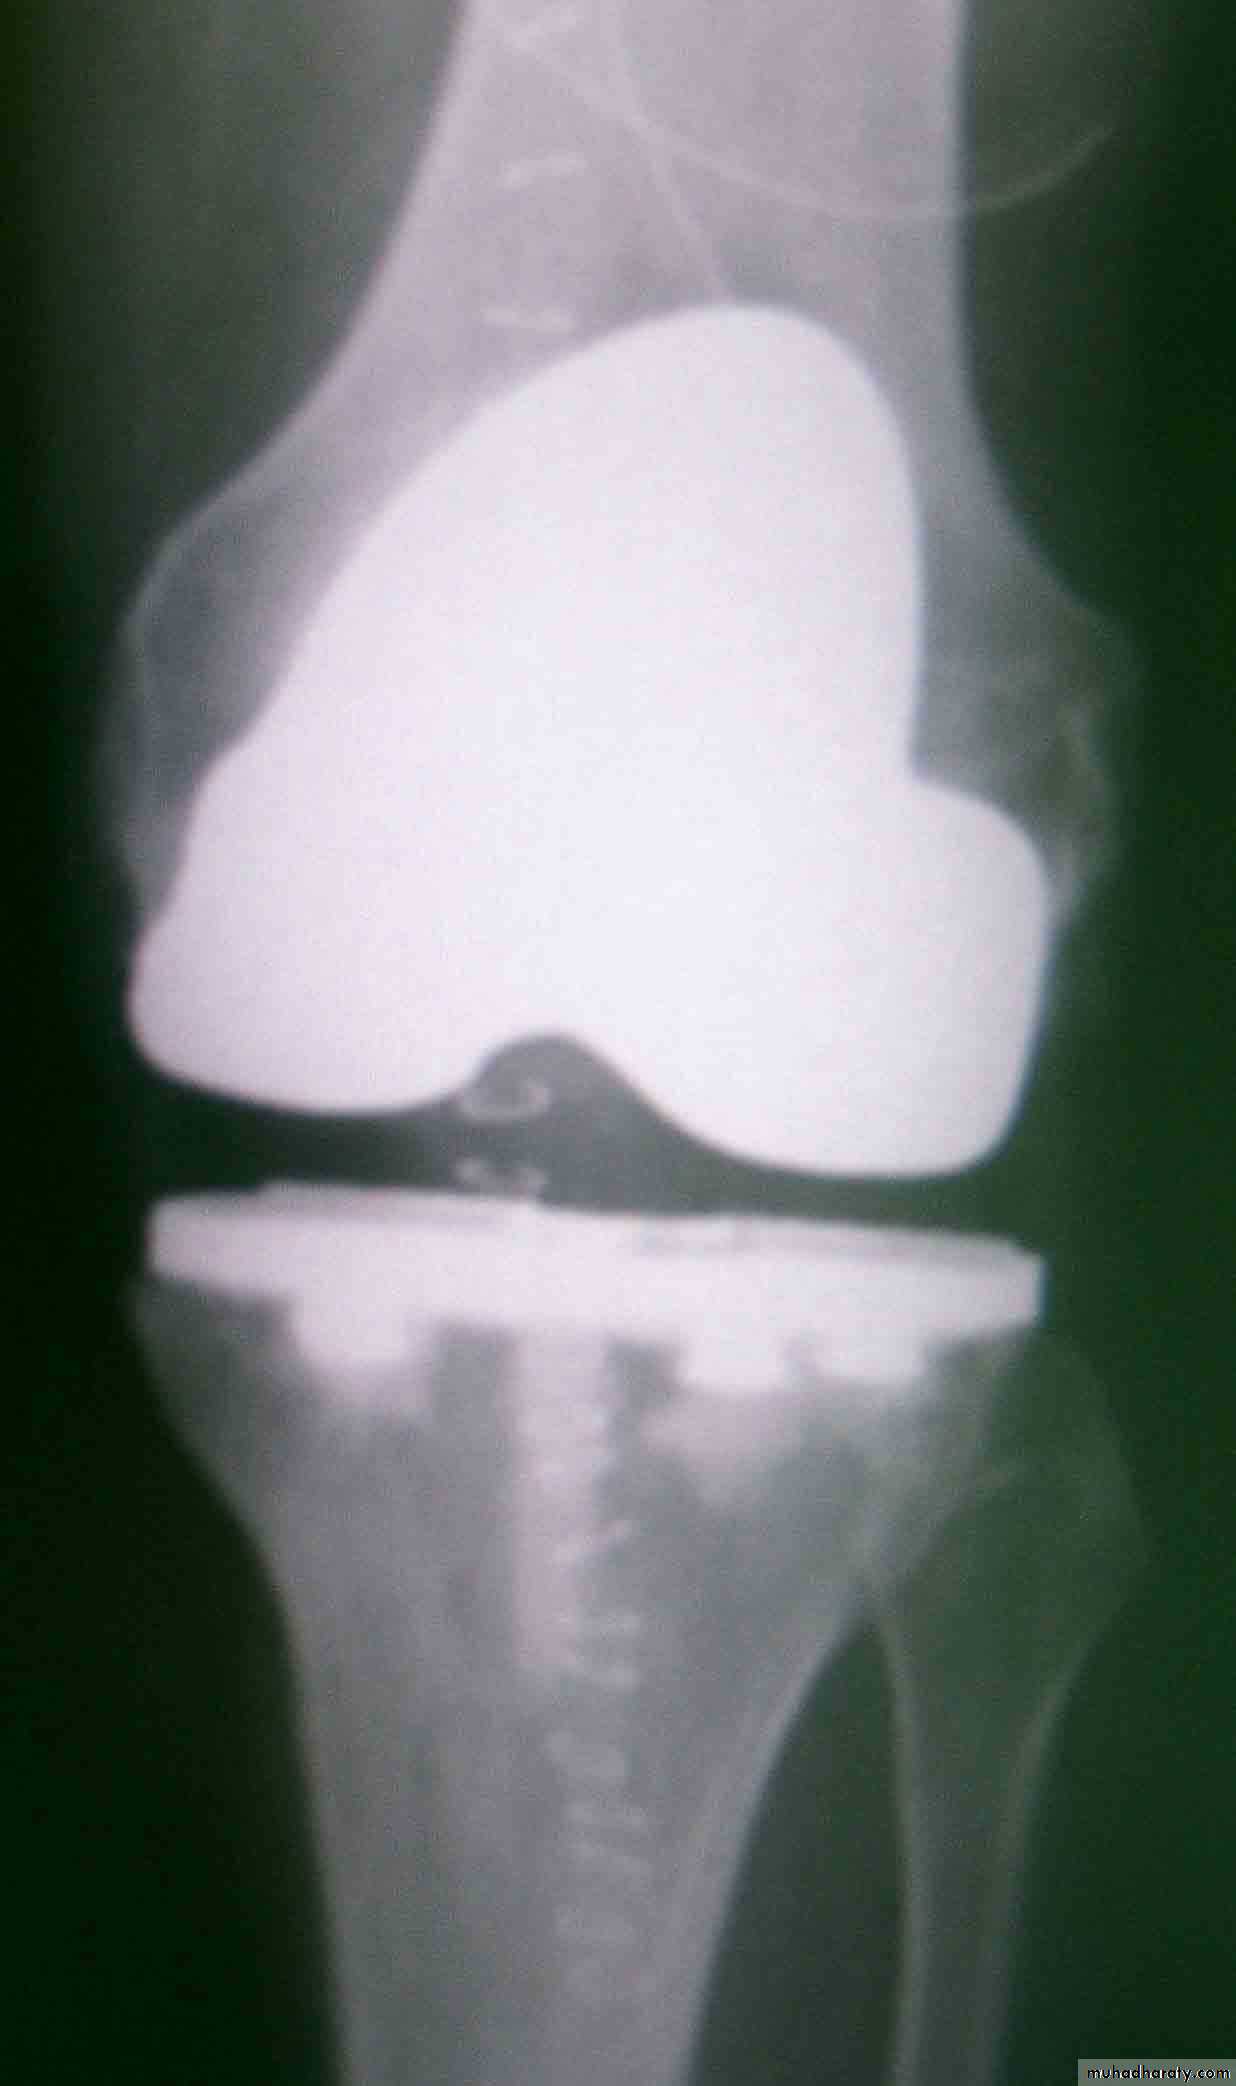

Arthrodesis or replacement arthroplasty may considers if articular surface is destroyed, years after healing, chemotherapy given 3 months before and after the operation.

arthrodesis

arthroplasty